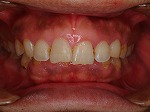

◆オールセラミック修復

~修復前~

オールセラミック修復

~修復後~

~修復後拡大~